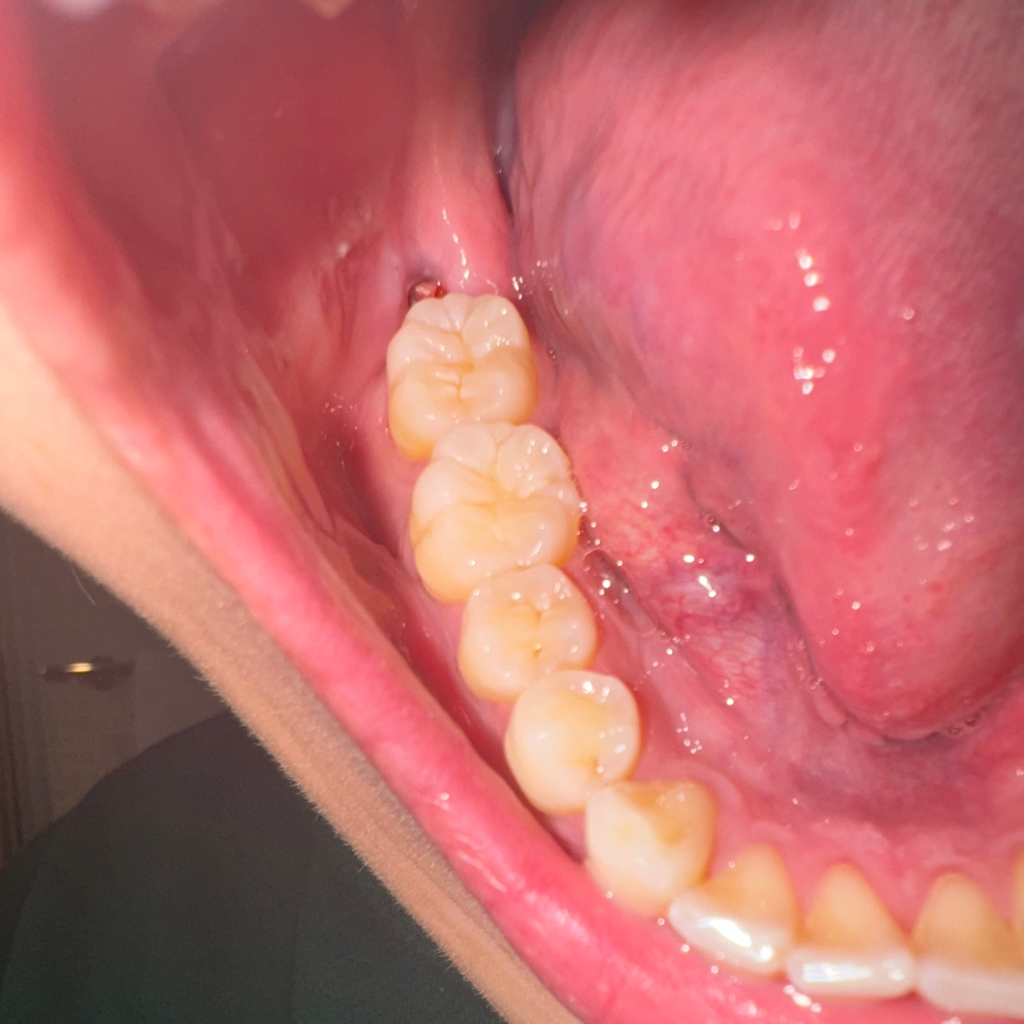

사랑니 발치 3주 후 가글 시 출혈

발치한지는 3주됐는데 음식물이 너무 깊게 많이 끼는 것 같아 가글을 좀 빡세게했는데 고춧가루같은 핏덩이..? 작은 핏덩이들이 우수수 나왔어요.. 통증도 없고 다시 가글하니까 안 나오는데... 혈병 탈락인건가요? 문제 없는지 궁금해요

가글 전후입니다

발치를 한 지 3주가 지났다면 이미 혈병은 사라지고 섬유화 과정을 거치고 있는 것으로 보여집니다. 사진 상에서는 정상적인 회복 과정으로 보여지며 아직까지 발치를 한 부위가 완전히 닫히지 않아 음식물이 끼어서 나타나는 현상으로 보여집니다. 시간이 지나면서 개선될 것으로 보입니다.